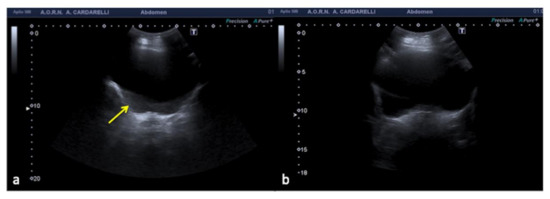

Figure 18. Longitudinal US pelvic scan (a) shows a small, triangular, hypoechoic area which may be misinterpreted as free fluid (arrows). On CT scan (b) it appears to be an intestinal loop (arrows).

Figure 19. Longitudinal US left flank scan (a) shows at the lower pole of the kidney (K) a hypoechoic area which may be misinterpreted as retroperitoneal free fluid (arrows) in a 22-year-old man investigated for trauma. On CT scan (b) it appears to be a spastic intestinal loop (arrow).